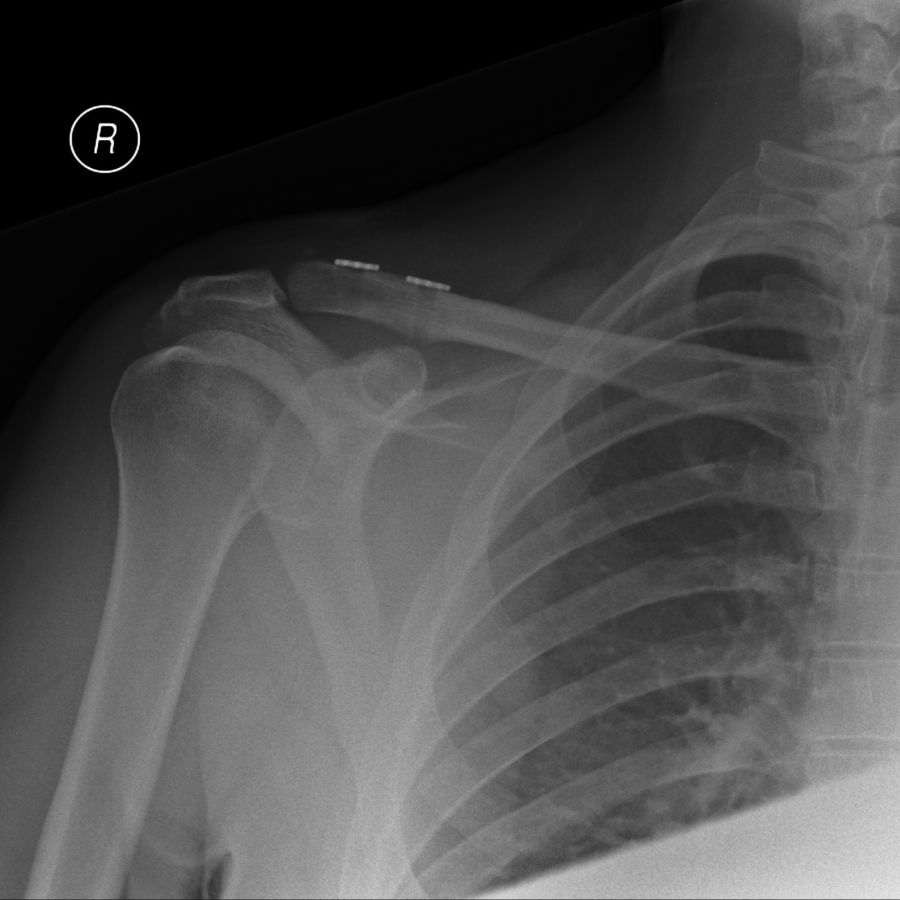

Acromioclavicular Joint Injuries

The acromioclavicular joint is a small joint between the outer end of the collar bone (clavicle) and the top of the shoulder blade (scapula). The joint is commonly injured by a fall on to the point of the shoulder. This can destabilise the joint and tear the ligaments which hold the joint in place. This allows the outer end of the collar bone to become prominent beneath the skin which can be seen and felt as a step or bump.

Treatment with surgery is considered for more severe injuries to the joint and in patients with physically demanding occupations or who are keen sportsmen or women. The damaged ligaments can be reconstructed soon after the injury and the clavicle held back in place using a specially designed suture that holds the clavicle in place.